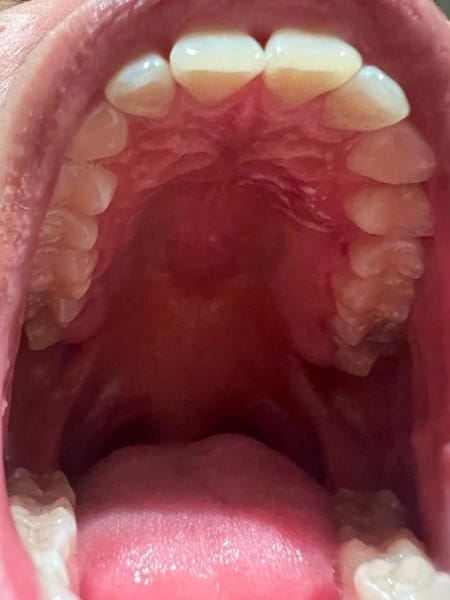

Pequeñas líneas blancas en el paladar duro, ¿Qué son?

Tengo unas pequeñas líneas blancas en el paladar duro, en un inicio pensé que fuese por alguna quemadura a algo que comí, pero al acercarme me di cuenta que estaba blanco y no parece ser un afta solo es en una pequeña area del lado izquierdo del paladar duro, todo el resto del paladar está sano, no me duele ni arde en el área, se siente igual que el resto del paladar, tampoco he tenido malestar físico o fiebre. Hace unos días tuve una reacción alérgica por algo que comí, tomé loratadina y me sentí mejor, no sé si esté relacionado. Hace un mes también comencé a tomar vitaminas centrum para tener mejores defensas ante el frío de invierno. Me preocupa porque soy fumador, no en exceso pero sí desde hace algunos años. Hago ejercicio constante. ¿Qué podría ser? Anexo fotografías.